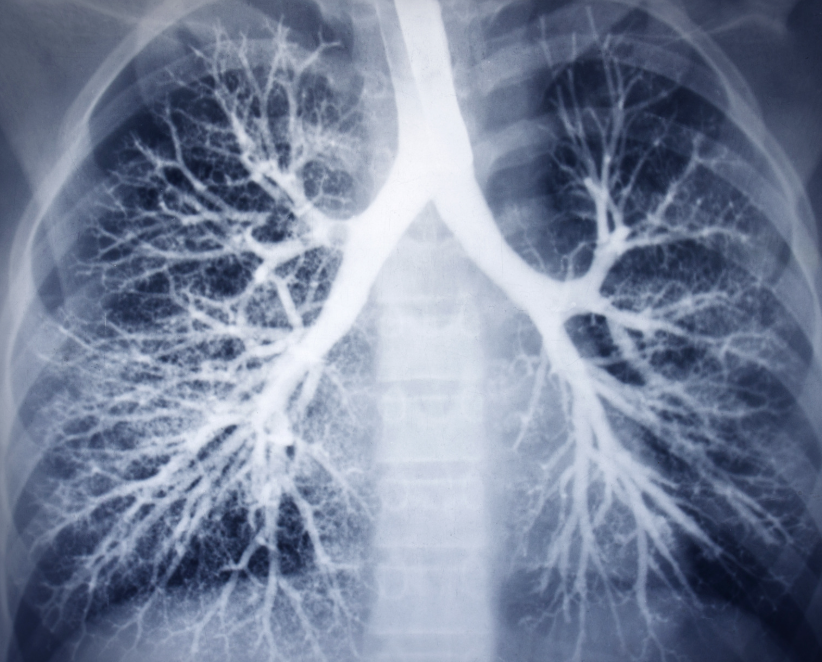

Płuca – najpoważniejsze powikłanie

Najgroźniejsze działania niepożądane dotyczą płuc. U części pacjentów może rozwinąć się śródmiąższowe zapalenie płuc a nawet włóknienie płuc. Objawia się ono narastającą dusznością, suchym kaszlem i spadkiem tolerancji wysiłku.

To powikłanie wymaga szybkiej diagnostyki, ponieważ nieleczone może prowadzić do trwałego uszkodzenia płuc.